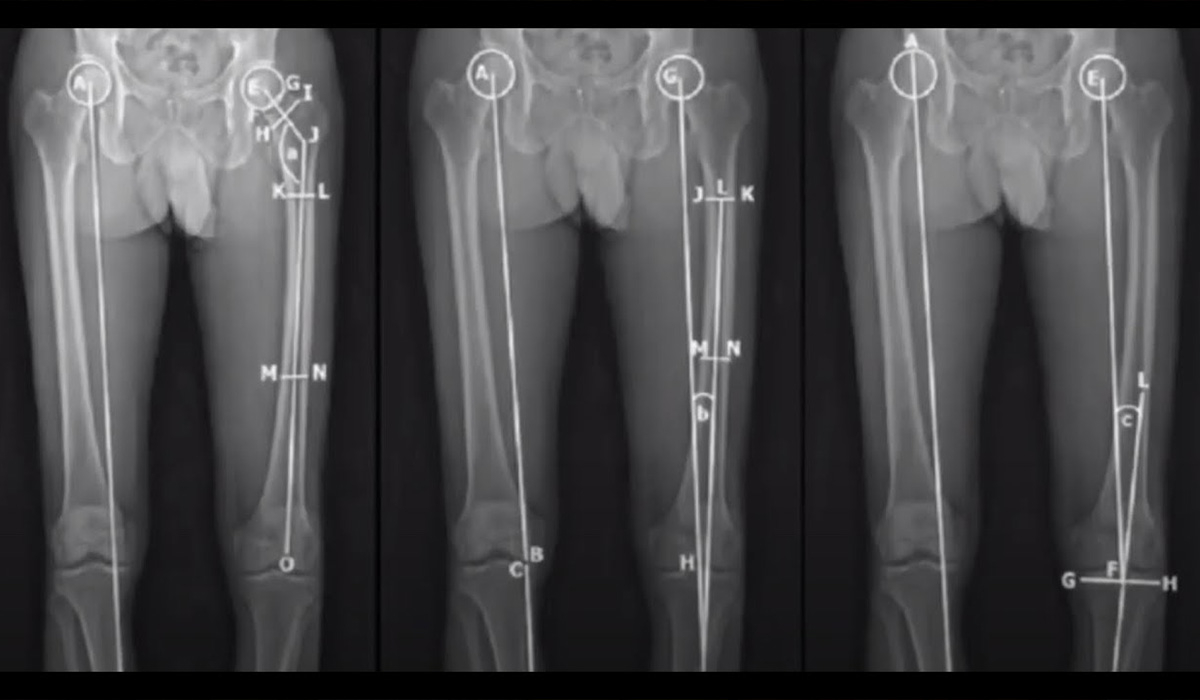

Одним з важливих аспектів сучасної ортопедичної хірургії є подовження і корекція осі нижніх кінцівок. Це хірургічні втручання, спрямовані на виправлення або зміну довжини та положення кісток у стопі та гомілці. Даний метод є надзвичайно важливим в лікуванні вроджених чи набутих вад структури нижніх кінцівок, які можуть впливати на здоров'я та функціональність опорно-рухового апарату. Одним з головних завдань косметичної хірургії є…